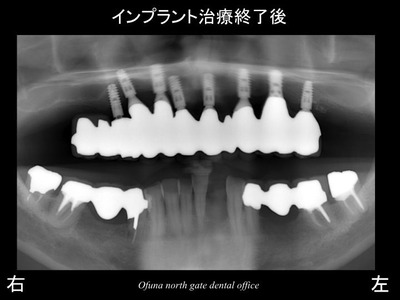

以下は、インプラント治療が終了した状態です。

使用したインプラントは、

アンキロス インプラント と

ストローマンインプラント(ITIインプラント)

です。